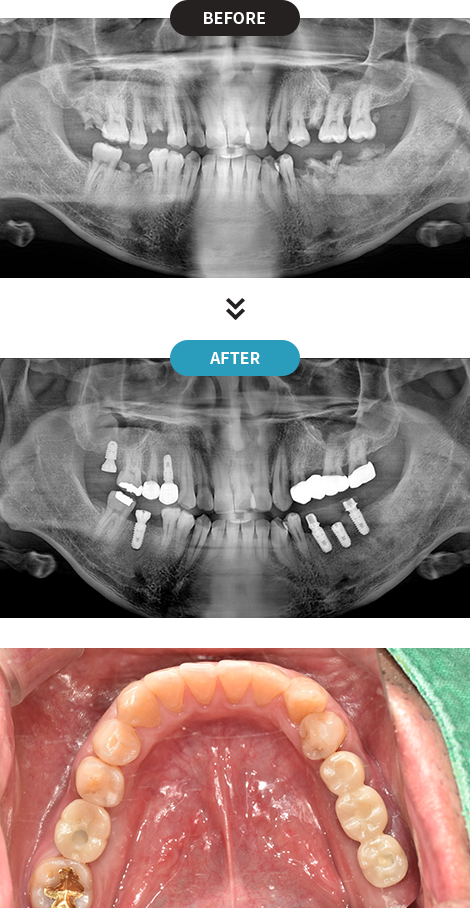

3D디지털 스캔을 활용하여 가장 안전하게 임플란트를

식립할 수 있는 위치를 0.1mm 오차까지 정확하게 계산합니다.

제작된 보철물을 모의 수술을 통해 정해진 임플란트 식립 위치에 빠르고 정확하게 식립합니다.